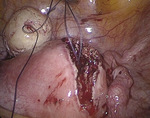

Po wytworzeniu odmy otrzewnej wprowadzono przez pępek trokar 10 mm, a następnie optykę laparoskopu i trokary dodatkowe w podbrzuszu 5 i 10 mm. Pacjentkę ułożono w pozycji Trendelenburga. Uwidoczniono powiększony trzon macicy, ścianę przednią uwypukloną przez mięśniak śródścienny o średnicy około 4-5 cm (ryc. 1), przydatki obustronnie bez zmian. Pozostałe narządy jamy otrzewnej dostępne wizualizacji laparoskopowej były niezmienione.